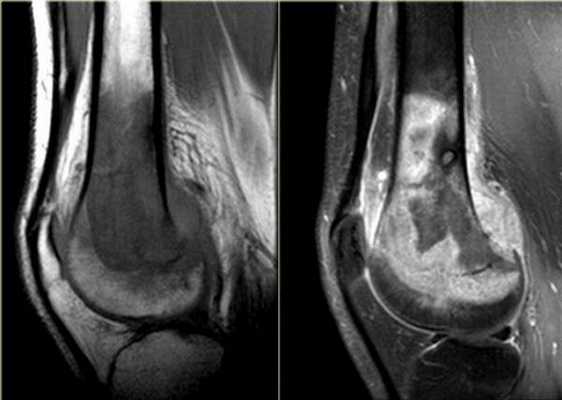

МРТ коленного сустава, разрыв передней крестообразной связки

МРТ колена: гонартроз